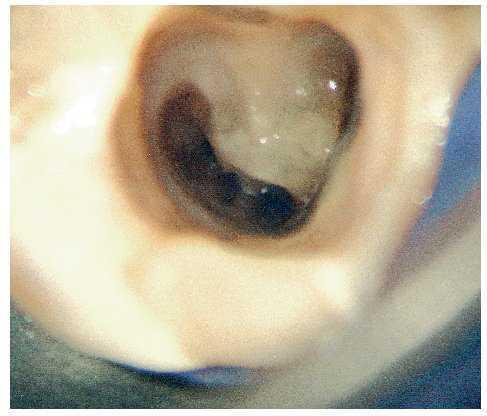

Figura 3a. Diente 21: radiografía diagnóstica: periodontitis apical con reabsorción del ápice radicular. La obturación del conducto radicular ofrece un aspecto tenue, pero con un sellado marginal correcto en sentido mesiodistal.

Figura 3b. Diente 21: situación clínica en el momento de la apicectomía: técnica con cono central en un conducto radicular ovalado. Se aprecia claramente la obturación insuficiente de la luz del conducto. Éste adopta una forma ovalada en sentido vestibulolingual, lo que no era visible en las radiografías.